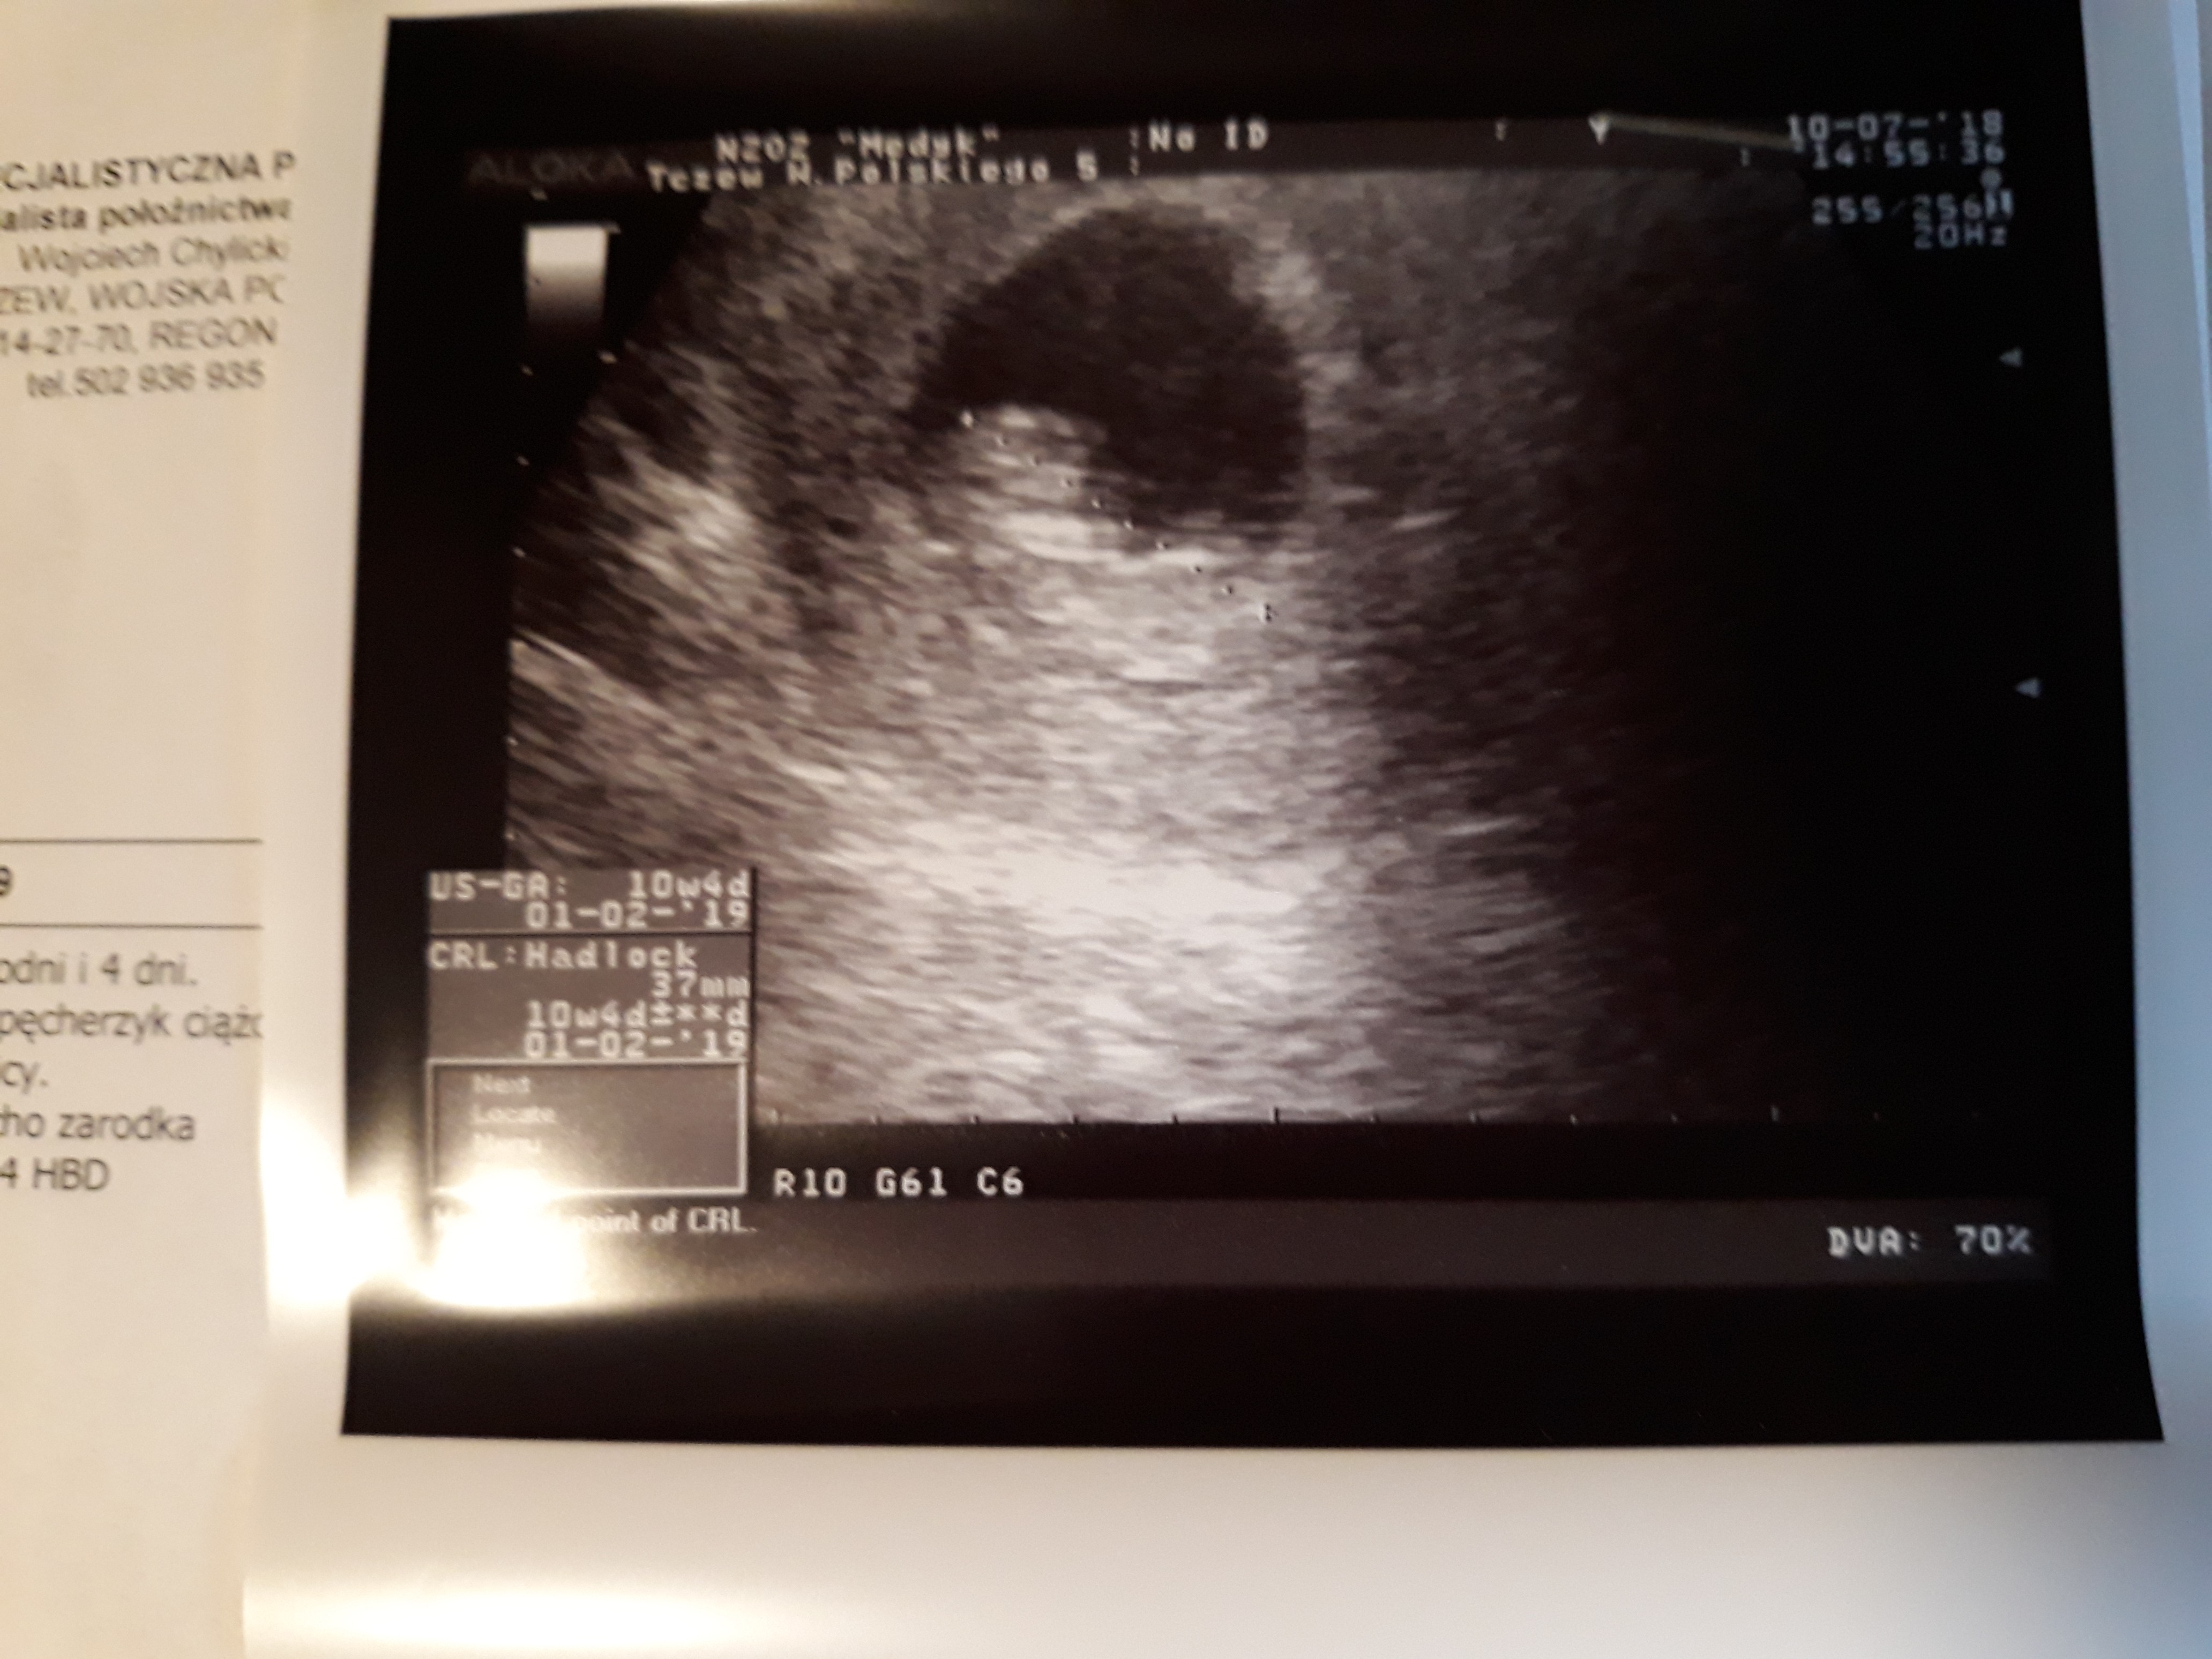

Ja też po wizycie . Wg om i usg 10 t.4 D. Dzidziuś ma już prawie 4 cm .

Z powodu że byłam z córka to usg przez brzuch i słabo było widać. Za 3 tygodnie kolejna wizyta z pomiarami.

• 20180710_183653.jpg

20180710_183653.jpg

1,5 MB · Wyświetleń: 101